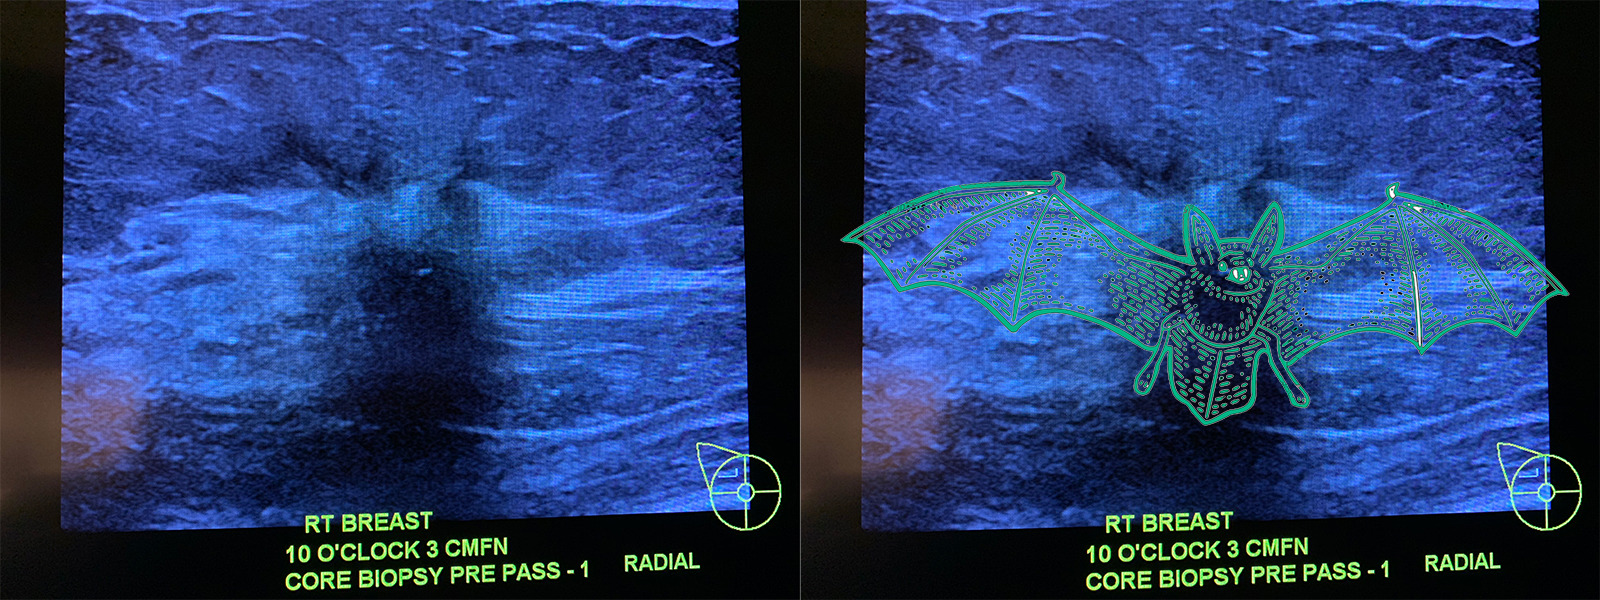

Then off to get the biopsy. With me was the ultrasound tech, nurse, Dr from trial, Dr to perform biopsy. Layed on a table so ultrasound could begin. When we looked at the pics I realized my cancer mysteriously resembles a bat..which, is now named Vlad.

Next,the Dr numbs the area, inserts needle DEEP in there because that’s where Vlad resides. Then another needle goes in and you hear clicking when they retrieve bits of Vlad for testing. Once they got 4 samples, they’re flash frozen to be sent to Boston so they can slice up the samples to examine cells. I then started Letrizole which Ill be taking for the next 2 weeks and the another biopsy to see progress. I was grateful that I had a ride. Sometimes you just have to admit you can’t do it by yourself.